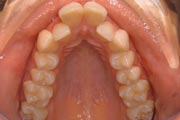

Crowding

Before